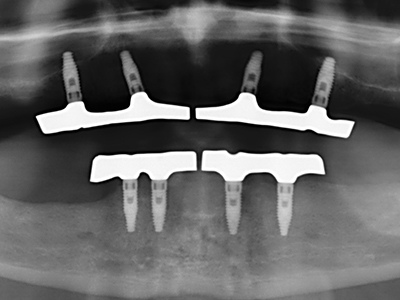

Fig. 11: El ortopantomograma posoperatorio presenta el aumento vertical y la elevación del suelo del seno.

Fig. 12: Después de seis meses de cicatrización se muestra una cresta maxilar vital con unas dimensiones suficientes en todas las direcciones.

Fig. 13: En este paciente de 52 años con una anchura del hueso residual del maxilar inferior de 4 mm, hay que asegurarse de que exista refrigeración por agua adecuada durante la partición del hueso.

Fig. 14: Incorporación de cuatro implantes RSX cónicos (Bego Implant Systems, Bremen).

Fig. 15: El control radiológico realizado al cabo de un año muestra una estabilidad del nivel óseo.

Fig. 16: También condiciones intraorales estables con incorporación de los implantes en la encía queratinizada.